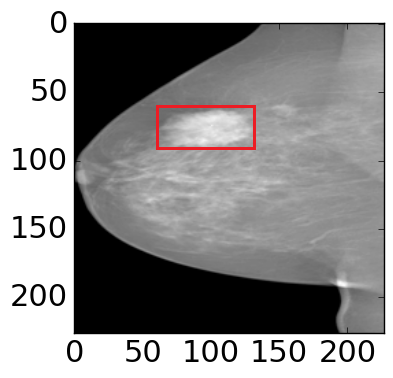

The shape and appearance prior play important roles in mammogram mass segmentation [29, 18]. The distribution of labels varies greatly with position in the mammographic mass segmentation. From observation, most of the masses are located in the center of region of interest (ROI), and the boundary areas of ROI are more likely to be background (Fig. 2(a)).

(a)

(b)